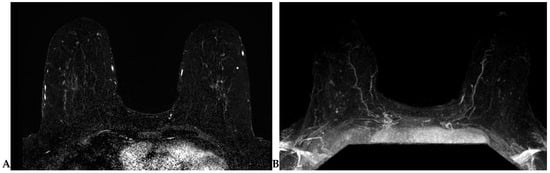

2.4.4. Background Parenchymal Enhancement (BPE)

2.4.5. Kinetic Curve Assessment